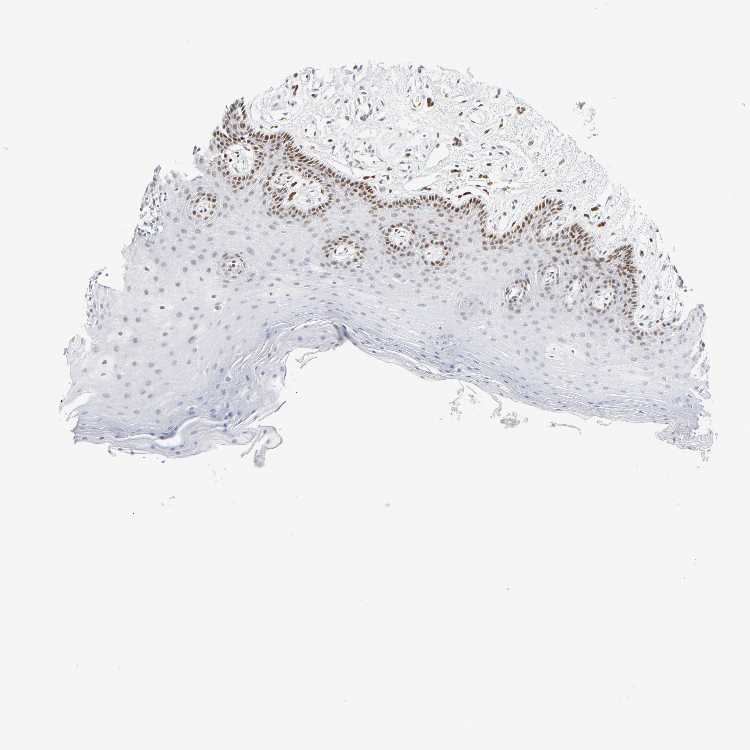

TISSUE PRIMARY DATA ORAL MUCOSA Show tissue menu

ORAL MUCOSA - Antibody stainingi

Antibody staining in the annotated cell types in the current human tissue is reported as not detected, low, medium, or high, based on conventional immunohistochemistry profiling in selected tissues. This score is based on the combination of the staining intensity and fraction of stained cells.

Each image is clickable and will lead to virtual microscopy that enables deeper exploration of all samples and also displays staining intensity scores, fraction scores and subcellular localization as well as patient and tissue information for each sample.

Antibody HPA052625Antibody CAB004300Antibody CAB004674

Squamous epithelial cells HighNot detectedLow